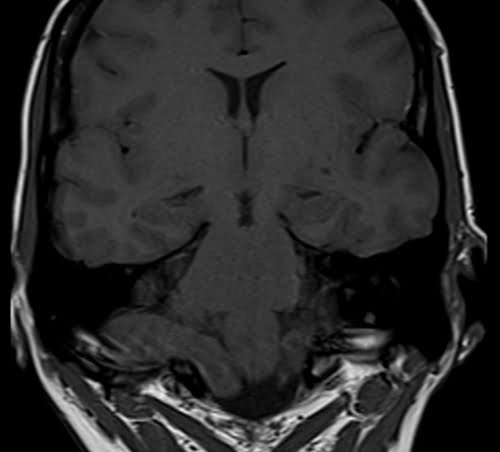

Brain epilipsy protocol mri coronal T1 images